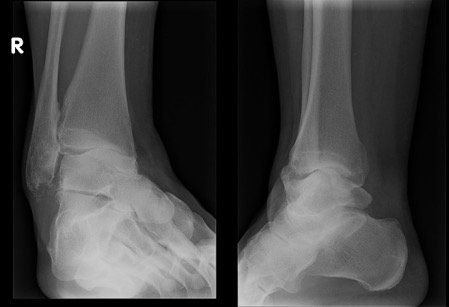

Arthritis of the ankle joint means there are degenerative changes within the joint. Degenerative changes are depicted by pain in the area, narrowing of the joint space, osteophytes or bone spurs, cystic areas within the bone, damage to the joint cartilage, and laying down of extra bone. There are many causes of ankle arthritis, ranging from simple wear and tear of the joint to more extensive injuries such as a bad ankle sprain or a motor vehicle accident.

Surgical treatment of ankle arthritis can involve cleaning out of the ankle joint, such as removal of damaged cartilage and bone spurs, to arthrodesis (stiffening) of the ankle joint, or an ankle joint replacement. The type of surgery proposed depends on the extent of the ankle arthritis and patient factors regarding recovery. Whilst Dr Julie Taranto and Mr Michael Taranto don’t perform ankle fusion or replacement procedures, they will be able to assess and advise you on the appropriate management and referral pathway via your GP.